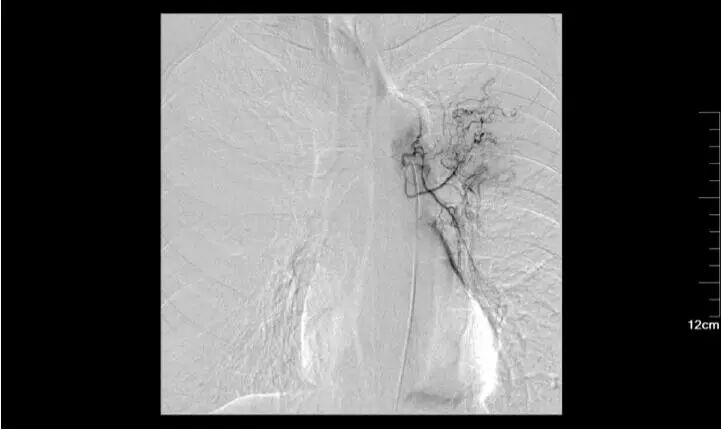

六 放射性粒子

射線對(duì)腫瘤具有殺傷作用,沒(méi)有射線殺不死的腫瘤,尤其是對(duì)射線敏感的腫瘤。介入醫(yī)生把具有放射作用的碘125粒子直接均勻的植入到腫瘤內(nèi)部,讓射線持續(xù)殺傷摧毀腫瘤。在最大限度降低對(duì)正常組織的損傷的同時(shí),卻又能達(dá)到殺死腫瘤的目的。

73歲肺鱗癌患者,拒絕手術(shù)和放化療,最后選擇放射性粒子植入術(shù),帶瘤生存5年。